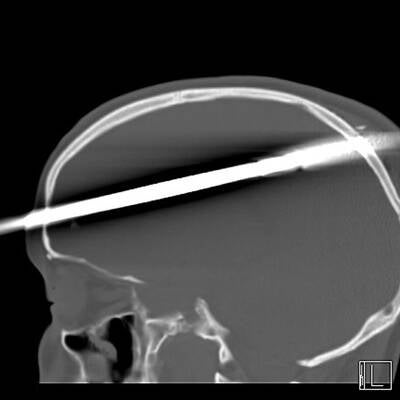

Es ist ein Wunder: Eine zwei Meter lange Eisenstange durchbohrte den Kopf von Eduardo Leite (24) aus Brasilien – und der Bauarbeiter hat es überlebt!

Ein wahres Wunder hat sich in Rio de Janeiro (Brasilien) ereignet: Eine Eisenstange stürzte aus gut 5 Metern Höhe auf den 24-jährigen Bauarbeiter Eduardo Leite. Ein Aufschrei bei seinen Kollegen, als sich die Stange durch seinen Helm hindurch in den Kopf bohrt und zwischen den Augen wieder heraustritt – ein Bild des Horrors!

In einer Notoperation kämpften die Ärzte um das Leben von Eduardo Leite. Sie öffneten den Schädel und entschieden sich, die Stange aus der gleichen Richtung zu entfernen, aus der sie in den Kopf eingedrungen war.